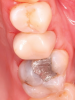

IOSs have found extensive applications across various dental specialties.1 In restorative dentistry, they are primarily used for fabricating dental restorations through CAD/CAM workflows, which remains by far their most widespread use (Figure 1 through Figure 5).2 The accuracy of IOSs enables dental professionals to produce restorations with precision that is on par with conventional methods.3 In addition to restorative dentistry, IOSs are being utilized for various applications in prosthodontics, orthodontics, forensic dentistry, and oral and maxillofacial surgery.

Fig 1 through Fig 5. Single-visit restoration of a maxillary second premolar following root canal treatment. Fig 1: Morphology-guided overlay preparation. Fig 2: IOS bite registration via imaging of buccal tooth surfaces. Fig 3: Preparation margin defined following IOS impression. Fig 4: Overlay design on the IOS platform, integrating adjacent tooth anatomy. Fig 5: Bonded overlay fabricated from CAD/CAM resin-based composite. Fig 6 through Fig 9. Digital workflow for guided endodontics using a digital twin, created by registering an IOI with CBCT data.

Figure 4

Figure 5